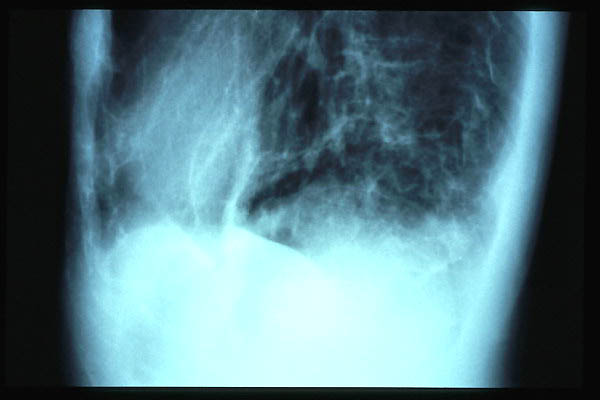

Calcificación de aórtica torácica.